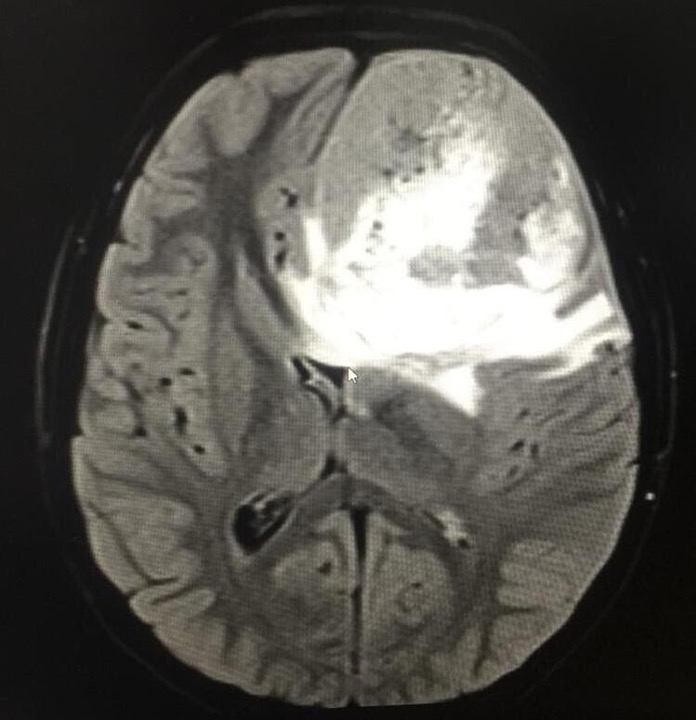

Cefalea en pediatría: tumor embrionario. Reporte de caso

Jose Miguel Suescun-Vargas, Jairo Alejandro Gaitán-Alfonso, Angélica Leonor Durán-Lara, Monica Paola Gutierrez Gaitan, Andrea Donoso-Samper, Javier Yesid Pinzon-Salamanca

40-45

DOI: https://doi.org/10.14295/rp.v55i1.297